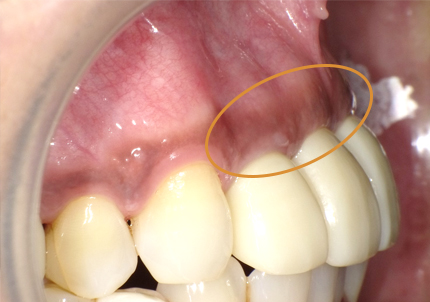

【左下5番ソケットシールドテクニック】

【ソケットシールドテクニックにて頬側骨の形態を維持する (右の様な骨のへこみを作らない)】

【通常の抜歯により唇側骨(外側の骨)が吸収してへこんだ症例】

※ 通常、ソケットシールドテクニックは前歯部領域に用いるが小臼歯部でも採用しました